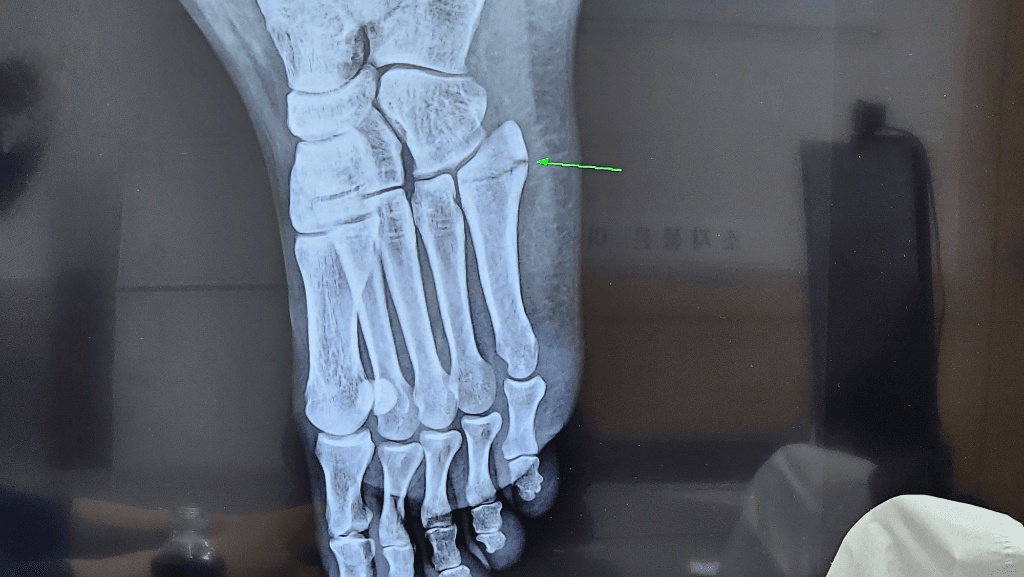

말씀하신 5번 중족골 골절은 끝쪽만 금이 간 경우가 많고 엑스레이에서 보이는 선이나 다른뼈나 혈관 그림자일 수도 있습니다. 다만 선이 더 벌어진 듯 보이고 의사도 당황했다면 골절이 진행되었거나 불안정한 상태일 가능성도 있습니다 정확한 판단은 엑스레이 판독 경험이 있는 전문의가 해야 하고 필요하면 ct나 mri를 추가로 촬영하는 것이 좋습니다!안녕하세요. 채홍석 의사입니다.

두번째 사진을 보면 중족골 base에 골절선이 길게 이어져 있는 것을 확인할 수 있습니다

첫번 째 사진보다는 훨씬 뚜렷하게 보이는 것 같습니다